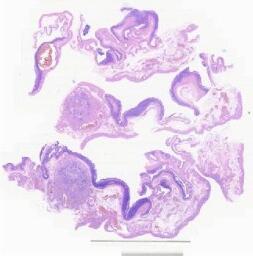

临床资料: 患者,女,50岁,异常子宫出血,B超示肌壁间一包块。宫腔镜见:宫体前位,宫腔深约7.5cm,宫颈管未见明显异常,宫腔下段见爱母环一枚,宫腔内膜粗糙,未见占位性病变,取环、诊刮后见宫腔形态正常,双侧宫角正常,双侧输卵管开口可见。腹腔镜见:子宫前位,宫体增大,子宫前壁近宫底部见实性包块凸出,直径约5.5cm,该包块形态规则,边界清楚,有假包膜,剖面呈旋涡状结构,双侧附件外观未见明显异常。

大体所见: 大体检查示:(子宫肌瘤)灰白、浅黄色不规则块状组织一块,大小8*4*3cm,切面呈灰白、浅黄色、实性、质中。

免疫组化: 无